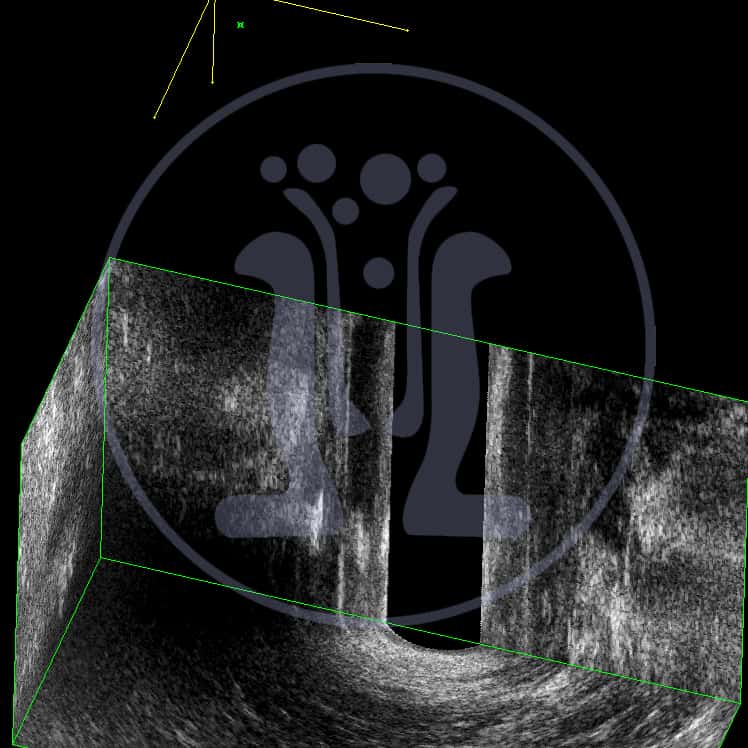

Ο Ι.Π. 85 ετών πατέρας φίλου ιατρού παρουσιάζει τσούξιμο στην περιοχή του πρωκτού. Μετά την τηλεφωνική συνομιλία αποστέλλεται με τηλεφωνικό μήνυμα, φωτογραφία της περιοχής του πρωκτού. Τίθεται η υποψία συριγγίου. Τελικά πείθεται ο ασθενής και προσέρχεται στο ιατρείο. Στο ιστορικό τελικά αναφέρεται ότι προ διμήνου υπήρξε πόνος ο οποίος παρήλθε μετά από εκροή υγρού. Η λεπτομερής κλινική εξέταση δείχνει στόμιο το οποίο και διερευνάται με ειδική μήλη. Το ενδοπρωκτικό υπερηχογράφημα με χρήση σκιαγραφικού αποδεικνύει την ύπαρξη συριγγίου, το οποίο είναι πολύ χαμηλό και δεν παρουσιάζει σημαντικό κίνδυνο.